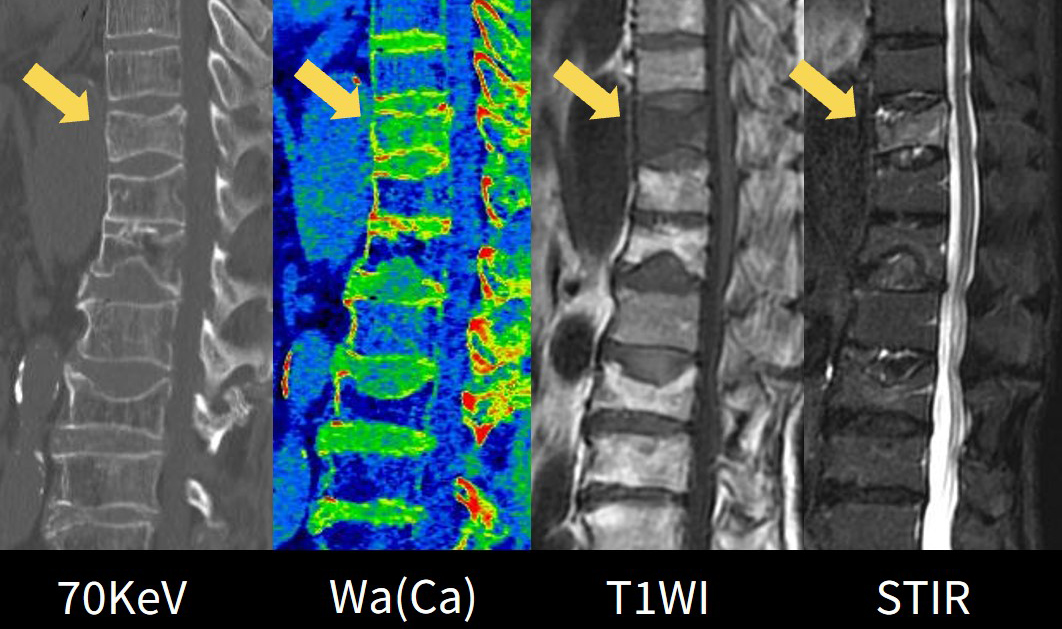

Wa(Ca)画像についての医師の評価

実際に運用を開始すると整形外科医からは、今までMRIで判断していた胸腰椎圧迫骨折の新鮮骨折か否かの鑑別や、レントゲンやSEでは判断が難しい不顕性骨折の評価がDEで短時間に撮影ができ、患者さんの負担も少なく判断できるととても高評価をいただきました。

また、Wa(Ca)の画像についても、臨床所見やSTIRとの比較画像(Fig5)から骨折部位の一致が見られるため信頼性が高いとの評価でした。

Frontier_Wakkanai05.jpg

Fig5. Wa(Ca)とMRIの比較画像